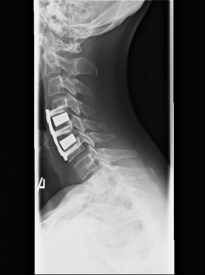

Spinalkanalstenose I

MRI with lateral reconstruction of the lumbar spine. The hourglass-like narrowing of the spinal canal can be seen at two heights.